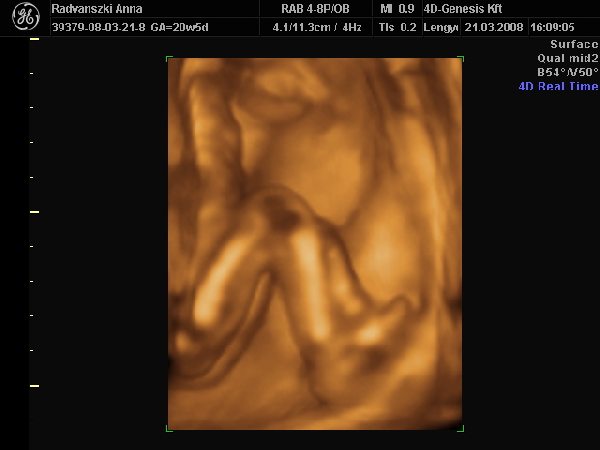

Nagyon szép kis lábai, combjai, feneke van, a szonográfus hölgy teljesen odáig volt meg vissza. Szó szó, tényleg kis formásnak tűnt.

Ja, és ez a hölgy is azt mondta, hogy nem lát semmit a lába között, úgyhogy kislány. A beterpesztés is elmaradt, de 2D-vel megnézte a hölgy, és azt mondta kislány.

lábikák